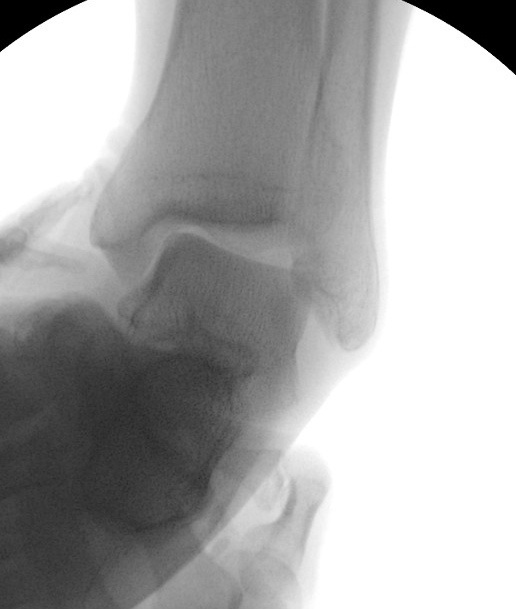

足関節が不安定な状態(足首を内側に捻ると関節の外側が開いている)